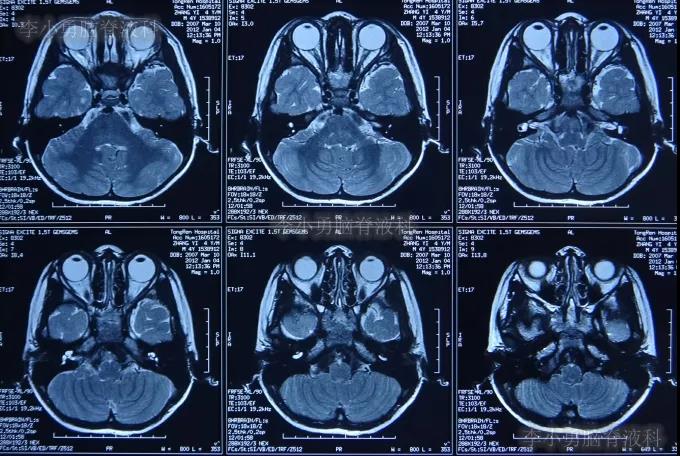

在5岁时2012年,为了进行人工耳蜗植入术,再次住入第1家的北京某著名三甲医院;在住院后的2012年1月4日,进行了术前必须的脑和颅底的核磁检查(图-2)。

图-2:2012年1月4日颅底和脑的核磁检查